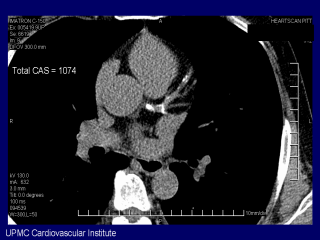

This patient, with really underwhelming traditional risk factors, had significant coronary calcification in his LAD and total coronary calcium score more than 1000.